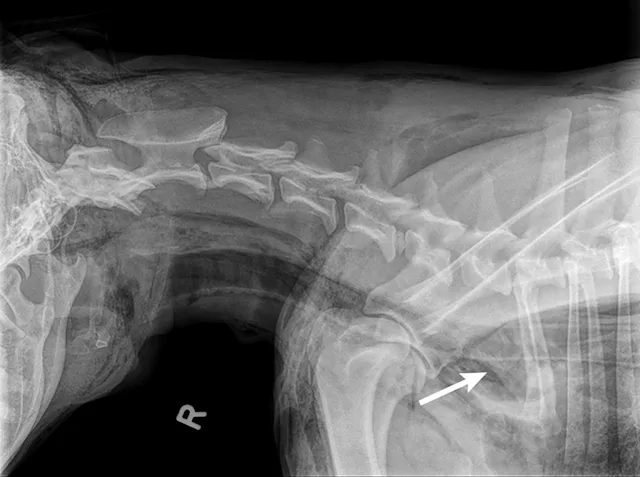

An x-ray of dog’s neck area with patches of radiolucent air in the soft tissue and in the cranial mediastinum.

Radiography should be conducted for wounds overlying the thorax or abdomen to look for intracavitary air that may warrant exploratory surgery. Thoracic radiographs should be evaluated for fluid outside the lungs (eg, hemothorax), pneumothorax, and/or rib fractures.3 Abdominal radiographs should be assessed for pneumoperitoneum. Areas between the stomach and diaphragm and ventral to the hypaxial muscles of the spine are common locations for detection of small amounts of air. Free air in the abdomen is a direct indication that emergency surgery is needed.